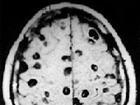

多发性脑梗死是指脑内有多个缺血性软化梗塞灶而言,又称为多发性脑软化。除常见的瘫痪、感受与言语妨碍外,还可能呈现痴呆。大夫们就将这种痴呆称为多梗塞性痴呆(即动脉软化性痴呆)。多发性脑梗死好发于50-60岁的男性,高血压以及动脉软化是次要病因。食物多样,谷类为主;多吃桃、橙、香蕉、菠菜...